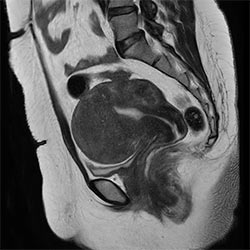

In a society where reimbursements are declining and chronic conditions lead to increased MR procedures and longer waiting times, there is ever increasing pressure on the radiology department. Today, further attempts to accelerate, compromise image quality or are limited to a narrow range of scans. Therefore, to meet the increased demand for productivity, a technology break-through in acceleration is still required. Leveraging our long standing leadership position in speed (i.e. SENSE), Philips brings compressed SENSE, a breakthrough in productivity.

Learn more about the main principles of Compressed SENSE and how it introduces a paradigm shift in productivity, how Compressed SENSE was designed around image quality, and how it advances productivity for clinical MR imaging.

Read about the experiences from Kantonsspital Winterthur (Switzerland) who experienced Compressed SENSE to be a simple yet powerful way to accelerate MRI scanning for different contrast types and sequences, in 2D as well as 3D.